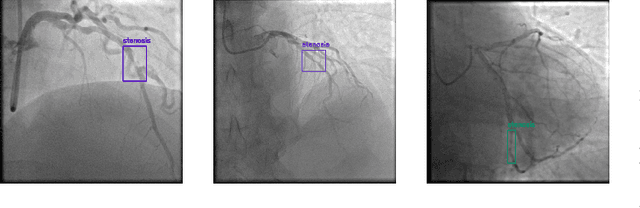

Detecting stenosis in coronary angiography is vital for diagnosing and managing cardiovascular diseases. This study evaluates the performance of state-of-the-art object detection models on the ARCADE dataset using the MMDetection framework. The models are assessed using COCO evaluation metrics, including Intersection over Union (IoU), Average Precision (AP), and Average Recall (AR). Results indicate variations in detection accuracy across different models, attributed to differences in algorithmic design, transformer-based vs. convolutional architectures. Additionally, several challenges were encountered during implementation, such as compatibility issues between PyTorch, CUDA, and MMDetection, as well as dataset inconsistencies in ARCADE. The findings provide insights into model selection for stenosis detection and highlight areas for further improvement in deep learning-based coronary artery disease diagnosis.